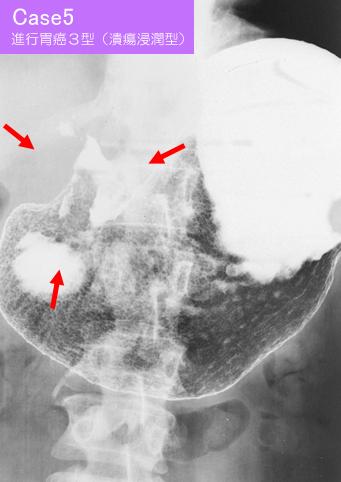

部位(臓器別)胃(部位)/前庭

検査方法X-P

腫瘍の肉眼分類3型(潰瘍浸潤型)/

病変の最大径(ミリ)40以上

腫瘍の深達度s(a)